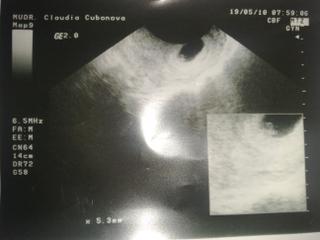

Miyya, děkuji za přivitání 😀 My jsme ještě na úplným začátku - zhruba v 5 týdnu - na utz byl zatim videt jen gest.váček. Byli jsme na utz brzo kvůli těm minulým problémum - mám skvělou doktorku, chtěla mít hned jistotu...Jinak nevíte někdo kde se dají stáhnout takové ty metříky ? Děkuji

dole máš napísane 5.3 mm, nebude to ono??to ste malinký na tvoj tt,ale ako pozerám je nás takých dosť. ale presne sa to určí v tom 12 tt. tam to bude zretelnejšie.